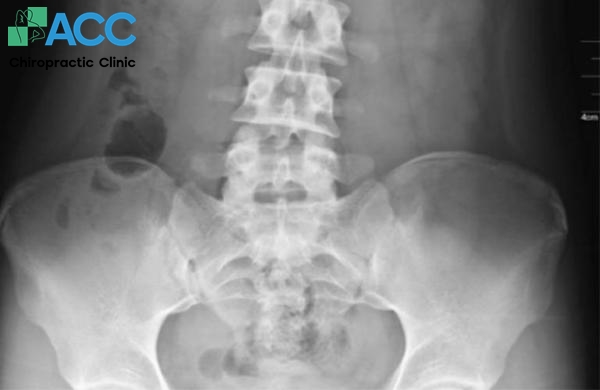

- Chụp X-quang: Có thể giúp bác sĩ loại trừ các nguyên nhân liên quan đến xương như gãy xương, tổn thương khớp háng hoặc thoái hóa.

- Chụp cộng hưởng từ (MRI): Phương pháp này cho hình ảnh chi tiết về cơ, gân và mô mềm giúp xác định chính xác vị trí, mức độ rách cơ háng.